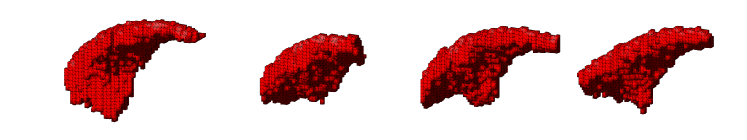

4.3.2 Analysing Heart Function in 4D MRI

Four-dimensional imaging of patient anatomy is gaining interest in the medical community. The temporal analysis of anatomical structures is used to extract the characteristics of related dynamic processes, which often indicate certain pathologies [16, 26, 3]. In this section, we apply nWESD to the shapes of the hearts extracted from four dimensional cardiac images of five different patients. The scan of each patient captures a full cycle of one heartbeat as a series of 20 3D images. Each image shows the left ventricle (LV) at a specific point in the cycle, from which we manually segment the corresponding blood pool. Our reference is the blood pool extracted from the first frame (diastole). We compute the nWESD scores between this reference and all other shapes extracted from the series of images. Here, we do not normalise the eigenvalues with respect to the global scale since size change is an important aspect of the heartbeat dynamics. The graph given in Figure 8 shows the results of these measurements over time across the five patients. The figure also shows some exemplary images and shapes. We observe that the symmetry of the heartbeat along the systolic (as the blood pumps out of the LV pool) and the diastolic phases (as the blood fills in the pool) is well captured with the nWESD score. Furthermore, the end-systolic phase (the time point with the largest distance w.r.t. the reference) is at different time points for different patients, which is to be expected since the different patient scans are not synchronized in time. In summary, WESD well captures the dynamics of the beating heart, which is to be expected given the continuous link between the differences in eigenvalues and the difference in shape (see Section 2).